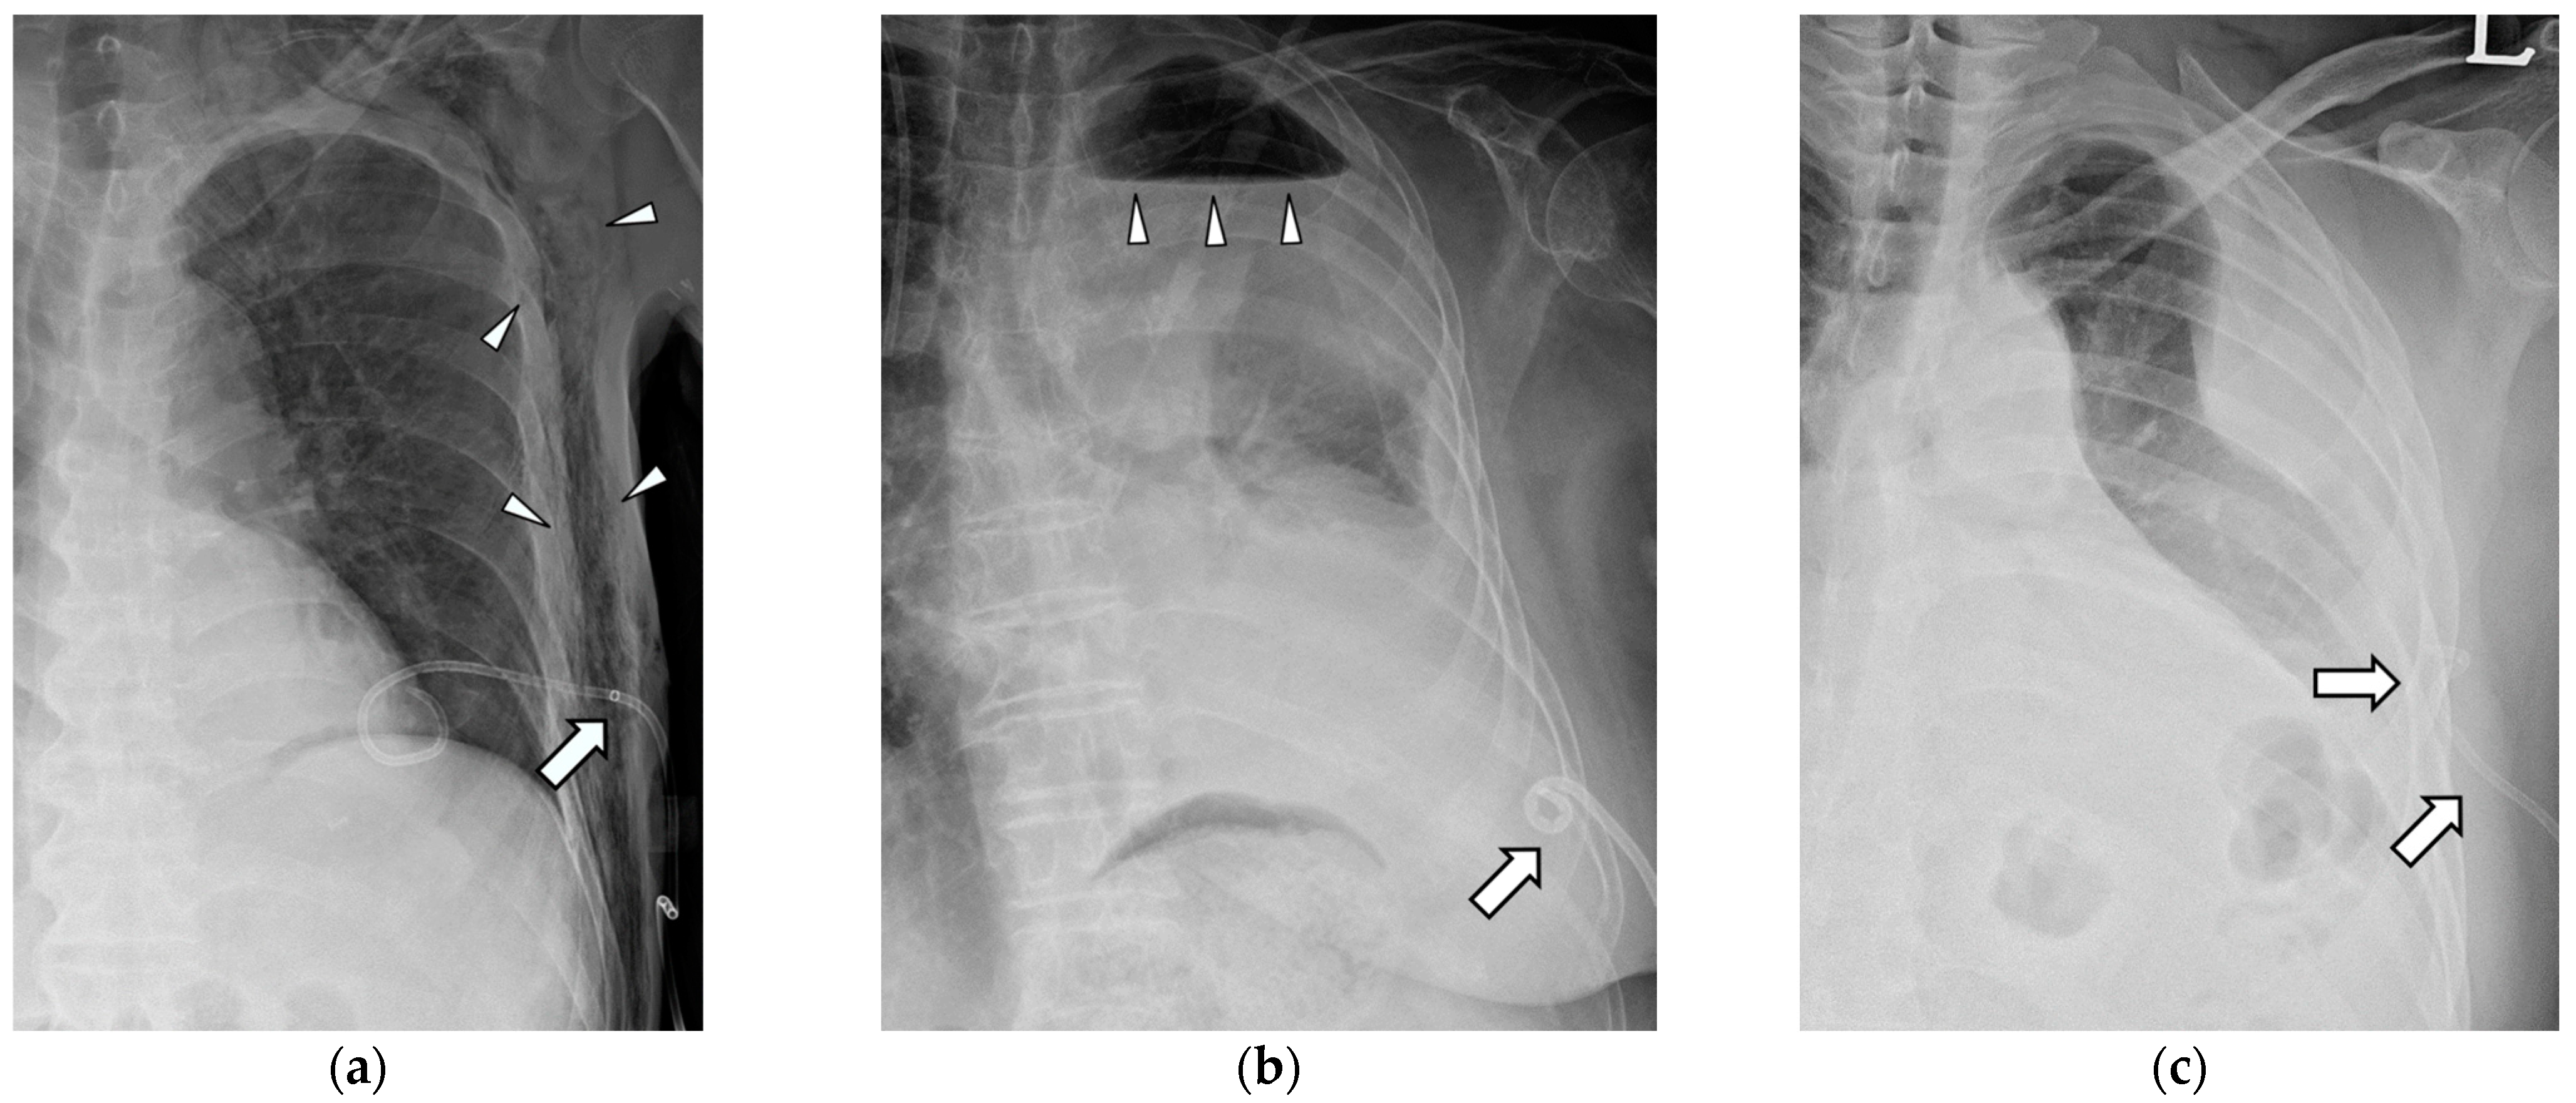

Technical success was defined as smooth drainage immediately after the successful installation of the catheter in the thoracic cavity with pleural effusion. Clinical success was defined as an improvement in pleural effusion upon follow-up simple chest radiography within 3 days without additional procedures. The indwelling time was defined as the catheterization period, and when the catheter was removed or changed because of complications, it was treated as censored data. Major complications included dysfunctional retraction, complete dislodgement, and blockage. Dysfunctional retraction was defined as the outward pulling of the distal pigtail loop of the catheter without leaving the pleural cavity, causing dysfunction in the drainage and replacement of the catheter (Figure 2a,b). Complete dislodgement was defined as the dislocation of the catheter end outside the pleural cavity where drainage fluid is located (Figure 2c). Blockage was defined as a rapid decrease in daily drainage with a significant amount of pleural effusion remaining in simple chest radiographs. Other complications, such as atraumatic pneumothorax (Figure 2b), hemorrhage, and subcutaneous emphysema (Figure 2a), were recorded for each catheter during the indwelling time. A pneumothorax refers to the presence of air in the pleural space, which is the space between the lungs and the chest wall. It can occur due to various reasons, including trauma or injury to the chest, lung diseases, or medical procedures. However, the reason for specifying it as an atraumatic pneumothorax was that the air accumulation in the pleural space was not caused by injury from the catheter but rather occurred independently due to various factors during the indwelling period.

There were three cases of complete dislodgement in the entire study population: two in the SPC group and one in the SPC + M group. One SPC + M catheter was continuously retracted (Figure 2a) and wholly dislodged from the pleural cavity. In the other two cases, patients unconsciously pulled out their catheters at night, and the catheters were missing in follow-up radiographs. However, complete dislodgement did not occur in the DPC group.

Dysfunctional retraction was most frequently noted in the SPC + M group, followed by SPC and DPC groups. In cases of SPC + M, catheter dysfunction was more likely to occur when some of the side holes at the mid-shaft were pulled outside the pleural cavity (Figure 2a). These pulled-out side holes can be blocked inside the chest wall and cause dysfunction, resulting in replacement. In addition, SPC can become dysfunctional when the pigtail loop is fully retracted and hangs onto the parietal pleura (Figure 2b). In contrast, when unintended traction occurred in DPC, additional pigtail coiling at the mid-shaft of the catheter prevented further retraction. The function of DPC was preserved by limiting the range of retraction (Figure 4a,b). Furthermore, while retraction of the midshaft coiling may occur, complete dislodgement of DPC was not observed.

Cases of subcutaneous emphysema and chest wall hemorrhage were observed exclusively in the SPC catheter. Subcutaneous emphysema is believed to be a complication resulting from the presence of multiple side holes in the shaft of the catheter, originally intended for efficient drainage. The positioning of these side holes in the chest wall during retraction is considered to be problematic (Figure 2a). Since subcutaneous emphysema caused great discomfort to the patient, it is regarded as a major complication. However, in the case of chest wall hemorrhage, it is believed to be caused by inadvertent contact with blood vessels beneath the ribs. This occurrence is not considered to be specifically related to the type of catheter used. The fact that it was only observed in 1 out of 382 pleural drainage procedures suggests the effectiveness of using a small-bore pigtail catheter instead of a chest tube.

Figure 2. Complications of conventional percutaneous drainage pigtail catheters. (a) The drainage pigtail catheter was retracted, and a radio-opaque marker (arrow) indicating the locations of side holes was positioned at the chest wall level. This resulted in catheter dysfunction and subcutaneous emphysema (arrowheads). (b) The single-pigtail catheter without side holes was fully retracted to the chest wall. Hydropneumothorax (arrowheads) was not resolved because of the malfunctioning of the catheter. (c) Dislodgement occurred at the pigtail’s tip located completely outside the pleural cavity (arrows).